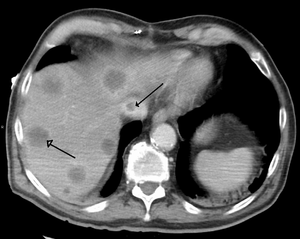

- Primary liver cancer most commonly manifests as hepatocellular carcinoma and/or cholangiocarcinoma; rarer forms include angiosarcoma and hemangiosarcoma of the liver. (Many liver malignancies are secondary lesions that have metastasized from primary cancers in the gastrointestinal tract and other organs, such as the kidneys, lungs.)[14]